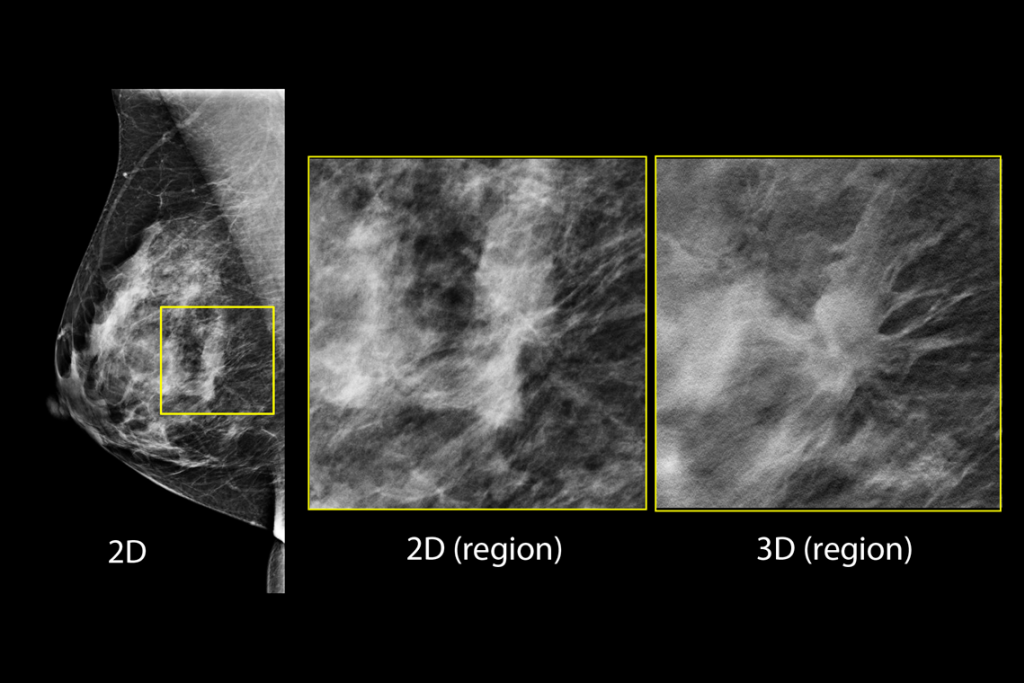

Imágenes clínicas de una mamografía con una lesión sospechosa

Imágenes clínicas de una mamografía